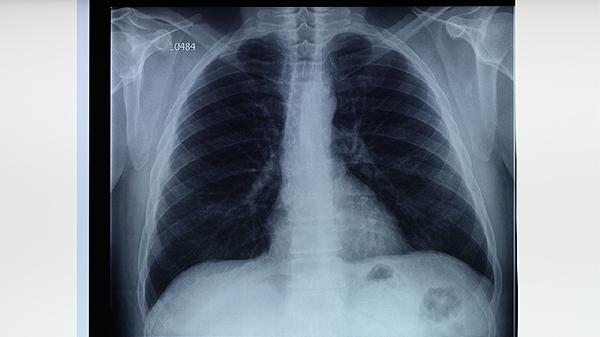

肺結(jié)核病的典型癥狀表現(xiàn)主要有咳嗽、咳痰、咯血、胸痛、發(fā)熱等。肺結(jié)核是由結(jié)核分枝桿菌感染引起的慢性傳染病,主要侵犯肺部,也可累及其他器官。

咳嗽是肺結(jié)核最常見的癥狀,早期多為干咳,隨著病情發(fā)展可出現(xiàn)咳痰??人猿掷m(xù)時間較長,通常超過2周,且普通止咳藥物效果不佳。肺結(jié)核患者的咳嗽多伴有午后低熱、夜間盜汗等全身癥狀。若出現(xiàn)長期不愈的咳嗽,應(yīng)及時就醫(yī)進(jìn)行結(jié)核菌素試驗或胸部X線檢查。

肺結(jié)核患者常出現(xiàn)午后低熱,體溫多在37.5-38.5℃之間,伴有夜間盜汗。發(fā)熱是機(jī)體對結(jié)核菌感染的免疫反應(yīng)。部分患者還可出現(xiàn)乏力、食欲減退、體重下降等消耗癥狀。長期不明原因發(fā)熱應(yīng)考慮肺結(jié)核可能,需進(jìn)行相關(guān)檢查明確診斷。